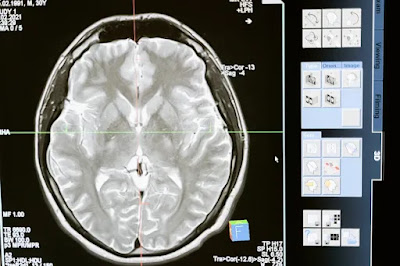

Ερευνητές από το Νοσοκομείο Brigham and Women’s στη Βοστώνη ανέπτυξαν ένα μικροσκοπικό εμφύτευμα που έχει σχεδιαστεί για να βοηθήσει τους γιατρούς να κατανοήσουν και να θεραπεύσουν καλύτερα τα γλοιώματα, έναν από τους συχνότερους καρκίνους του εγκεφάλου. Τα γλοιώματα είναι μια ομάδα όγκων του κεντρικού νευρικού συστήματος που διαφοροποιούνται ανάλογα με τα εγκεφαλικά κύτταρα από τα οποία προέρχονται, καθώς και το βαθμό επιθετικότητας.

Το νέο εμφύτευμα έχει το σχήμα και το μέγεθος ενός κόκκου ρυζιού και έχει σχεδιαστεί για να χρησιμοποιείται κατά τη διάρκεια χειρουργικής επέμβασης. Μπορεί να διεξάγει δεκάδες πειράματα ταυτόχρονα, προσφέροντας ακριβή εικόνα στους γιατρούς για τις επιδράσεις των φαρμάκων στους όγκους.

Το εμφύτευμα τοποθετείται μέσα στον όγκο για δύο με τρεις ώρες και δοκιμάζει έως και 20 φάρμακα. Αυτό δίνει στους γιατρούς μια ακριβή ιδέα στο πώς αντιδρά ο όγκος σε κάθε θεραπεία. Οι πληροφορίες που συλλέγει η συσκευή αποστέλλονται σε εργαστήρια για μελέτη.

Έξι ασθενείς δοκίμασαν αυτή τη συσκευή κατά τη διάρκεια χειρουργικής επέμβασης. Κανείς ασθενής δεν εμφάνισε παρενέργειες και οι ερευνητές κατάφεραν να συγκεντρώσουν πολλές πολύτιμες λεπτομέρειες σχετικά με το πώς αντιδρούσαν οι όγκοι στις διάφορες θεραπείες. Αυτές οι πληροφορίες σε πραγματικό χρόνο μπορούν να βοηθήσουν στην προσαρμογή των θεραπευτικών επιλογών, καθιστώντας τες πιο αποτελεσματικές για κάθε ασθενή.